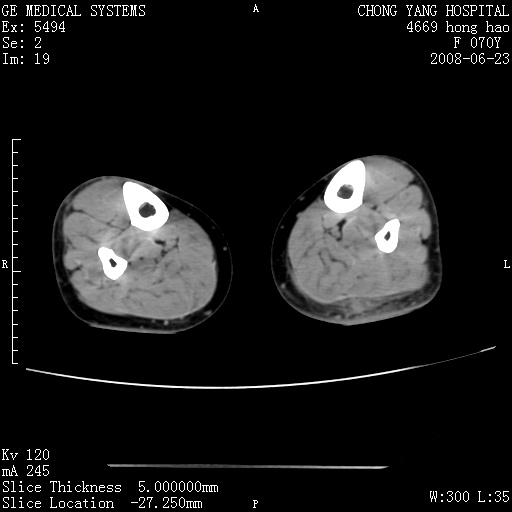

以下是引用zsl6918在2008-6-24 23:07:00的发言:[br]皮下脂肪影模糊,密度增高,但未见具体肿物影,考虑蜂窝组织炎可能性大。

以下是引用zjzjr在2008-6-24 21:44:00的发言:[br]皮下软组织肿厚,脂肪间隙混浊,考虑感染.

以下是引用peijunlong在2008-6-24 20:56:00的发言:[br]左小腿后方软组织皮下脂肪间隙见条片状密度增高影,范围较大,相邻皮下见条索影。[br]考虑:无菌性炎症可能性大[br]鉴别:主要与蔓状血管瘤鉴别,蔓状血管瘤也可表现为软组织内葡伏生长的扁平状的软组织密度影,但它的范围更大,且主要在软组织内,肌间隙中,皮下脂肪间隙内罕见。